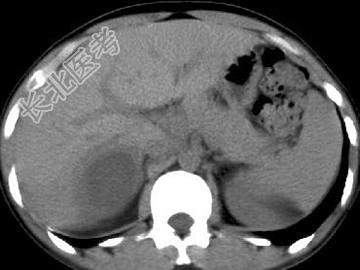

- 根据所提供的图像,最可能的诊断是 (